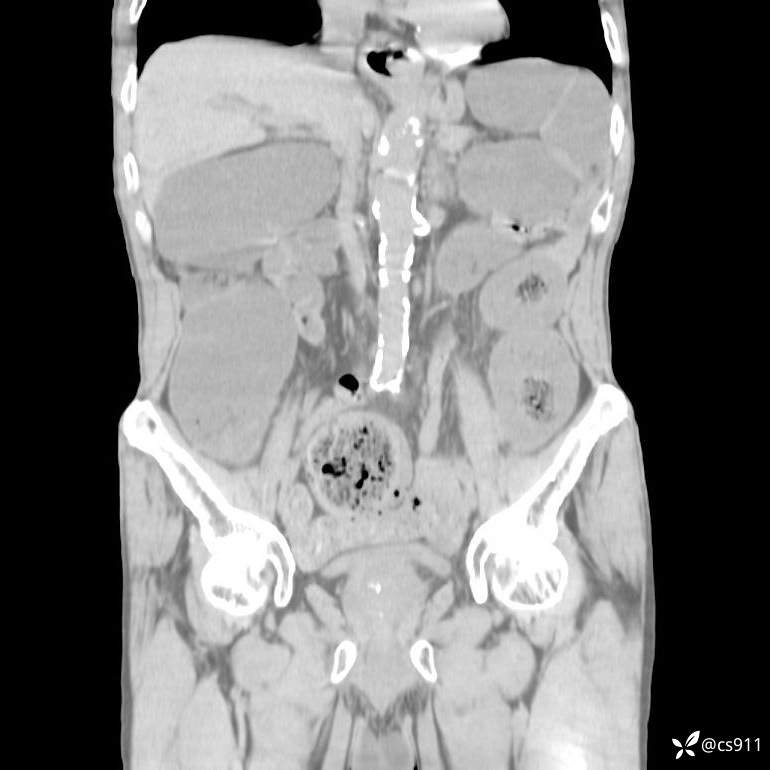

急腹症之急诊CT,原因?答案公布

男,77岁,腹痛、腹胀伴恶心呕吐1天。呕吐胃内容物,非喷射性呕吐,有咖啡色样胃内容物,诉有胃穿孔病史。查体:全腹平,下腹部压痛,全腹无反跳痛,叩诊呈浊音,移动性浊音阴性,肠鸣音减弱,1-2次/分。肛检:直肠未扪及明显肿物,可触及大量粪块。

T 36.6℃ P 80次/分 R 26次/分 BP 100/60mmHg

白细胞(WBC) H 14.55 10e9/L 4-10

中性粒细胞百分率(NEUT%) H 85.7 % 40-75

血淀粉酶(AMY) HH 1859 U/L 35-135

癌胚抗原(CEA) H 27.44 ng/ml 0-5

呕吐物 潜血试验 * 阳性 阴性

患者轮椅入室检查神志清楚, 能配合摆位和呼吸